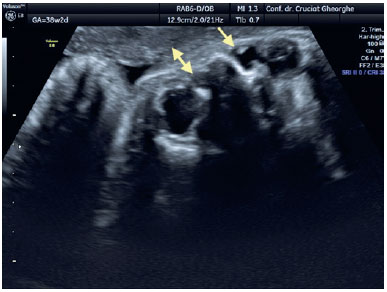

Examination of the fetal cephalic pole using fetal ultrasound performed at 31 WG revealed the presence of a 3-mm, liquid-filled, hypoechoic cyst located inferiorly and separated from the right eye ball (Figure 1). At 33 WG, the cystic lesion had enlarged (6/4.5 mm); however, it remained well demarcated from the eye ball and the nasal fossa. At the 36 WG follow-up examination, the dimensions of the right cyst were 8/7 mm and a similar lesion of 6/4.5 mm was identified contralaterally (Figure 2). At 38 WG, the DCC on the left side diminished and its content became more dense/opaque, whereas the structure on the right side maintained its liquid content and increased in size to 8/8.5 mm (Figure 3). All ultrasound examinations were performed using a Voluson E8 ultrasound system (GE Medical Systems, Zipf, Austria). Elective Cesarean section was performed at 39 WG, without perioperative complications. The newborn weighed 3,800 g, with an Apgar score of 10.